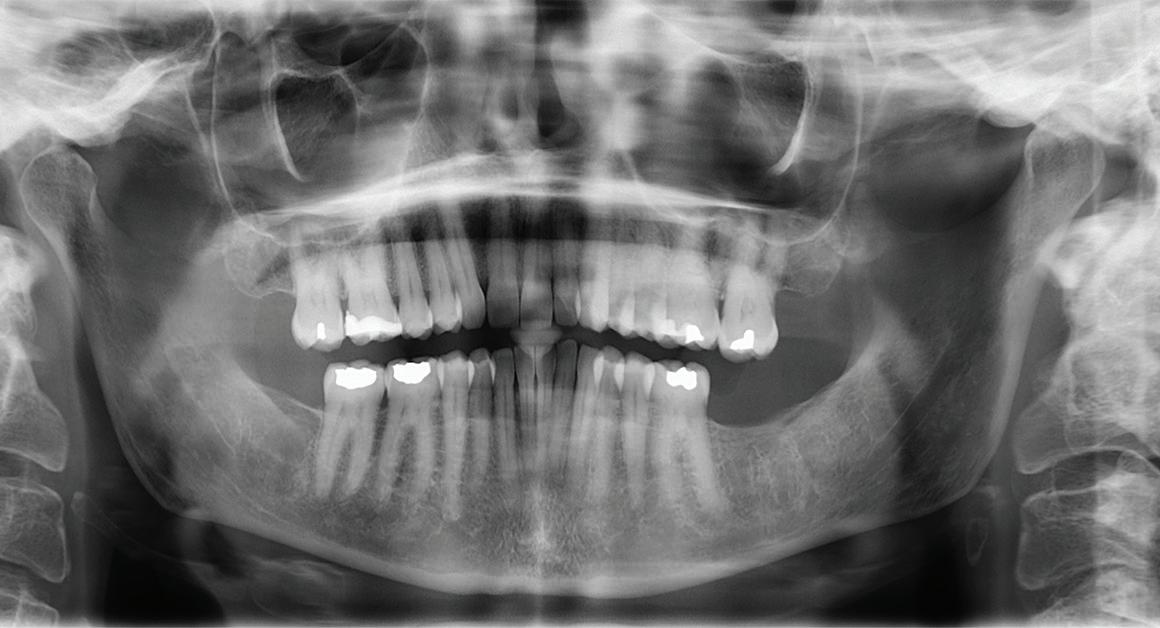

33 Oral Medicine, Oral Diagnosis, Oral Pathology

Pathologic jaw lesions associated with impacted teeth

Saede Atarbashi-Moghadam

Yaser Safi